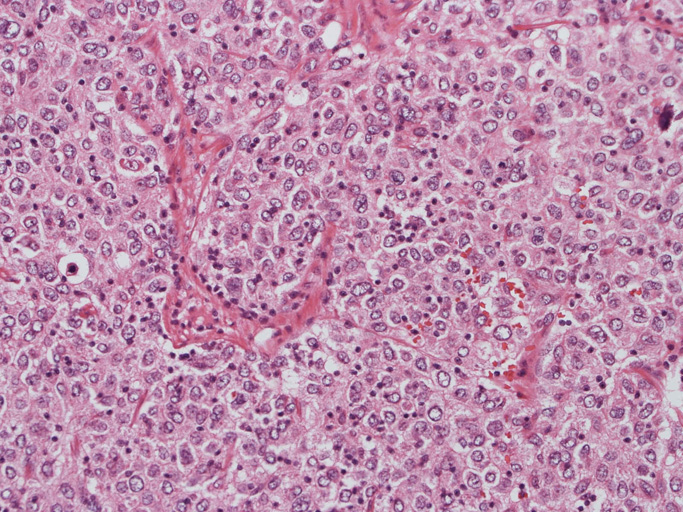

30歳代男性/ 大網腫瘍

上腹部圧迫感で受診. 画像所見で大網に13x11cmの腫瘤を認める。腫瘍摘出および膵脾合併切除術が行われる。腫瘍本体は網嚢内に位置. daughter lesionが複数認められた。膵脾には浸潤なし。リンパ節転移あり。6ヶ月後に腹膜播種で再発。

腫瘍は, 細血管を含む細い線維組織束で分画された胞巣状充実性病変で(Fig01),類円形ないし卵円形のvesicularな核をもつ円形, 多稜形の細胞が増殖している。核小体は小型, やや不明瞭。細胞質は境界が不鮮明で好酸性泡沫状を呈するものが多い。大型核やbizzarreな核の出現も認められる(Fig02-05)。血管周囲にリンパ球浸潤が認められる部分がある(Fig06,07)。